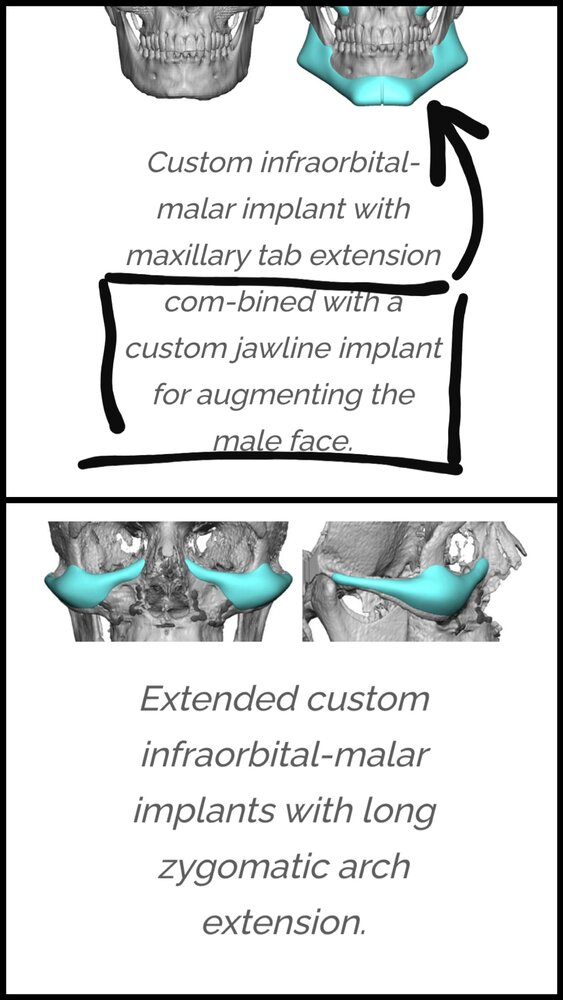

1. Implants *